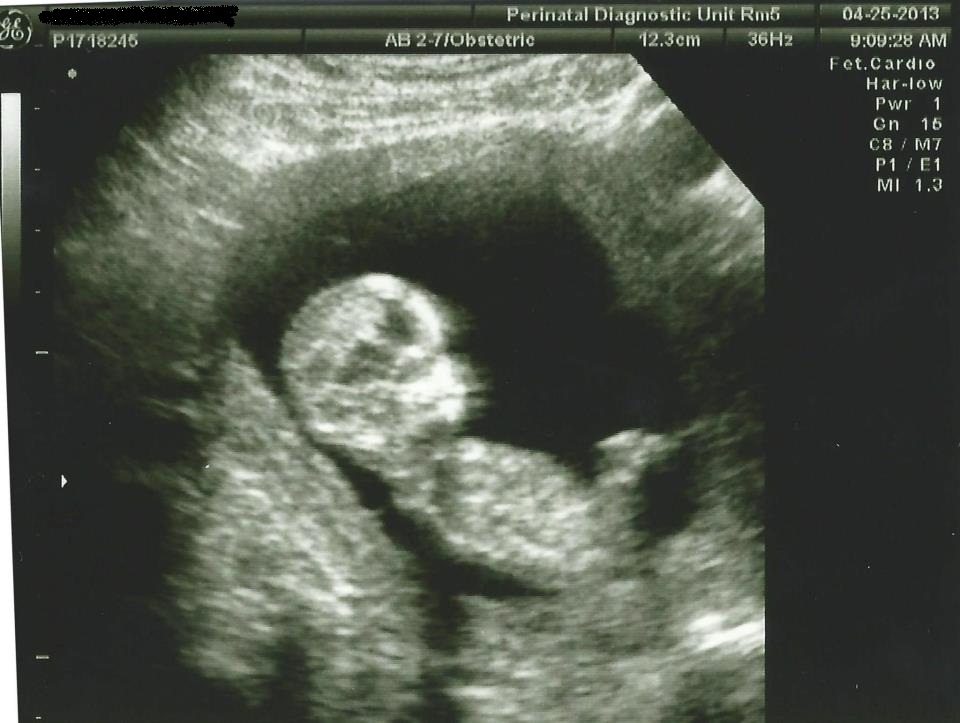

I've attached my NT scan from yesterday, 13 weeks, 0 days. The tech gave us her guess as to the sex of the baby, saying that she was 70% sure, but don't go painting the nursery just yet! We aren't holding her to it of course, but we are curious to see if it correct when we find out officially at 19 weeks! Could any of you ladies tell me your best guesses as to what you think the sex is based on this picture? This was the best one we got, not sure if it shows a clear view of any "nub" at all or not? I've only started reading about the skull theory, but I'd happily entertain any guesses based on that as well! :-)

Attachment 10864